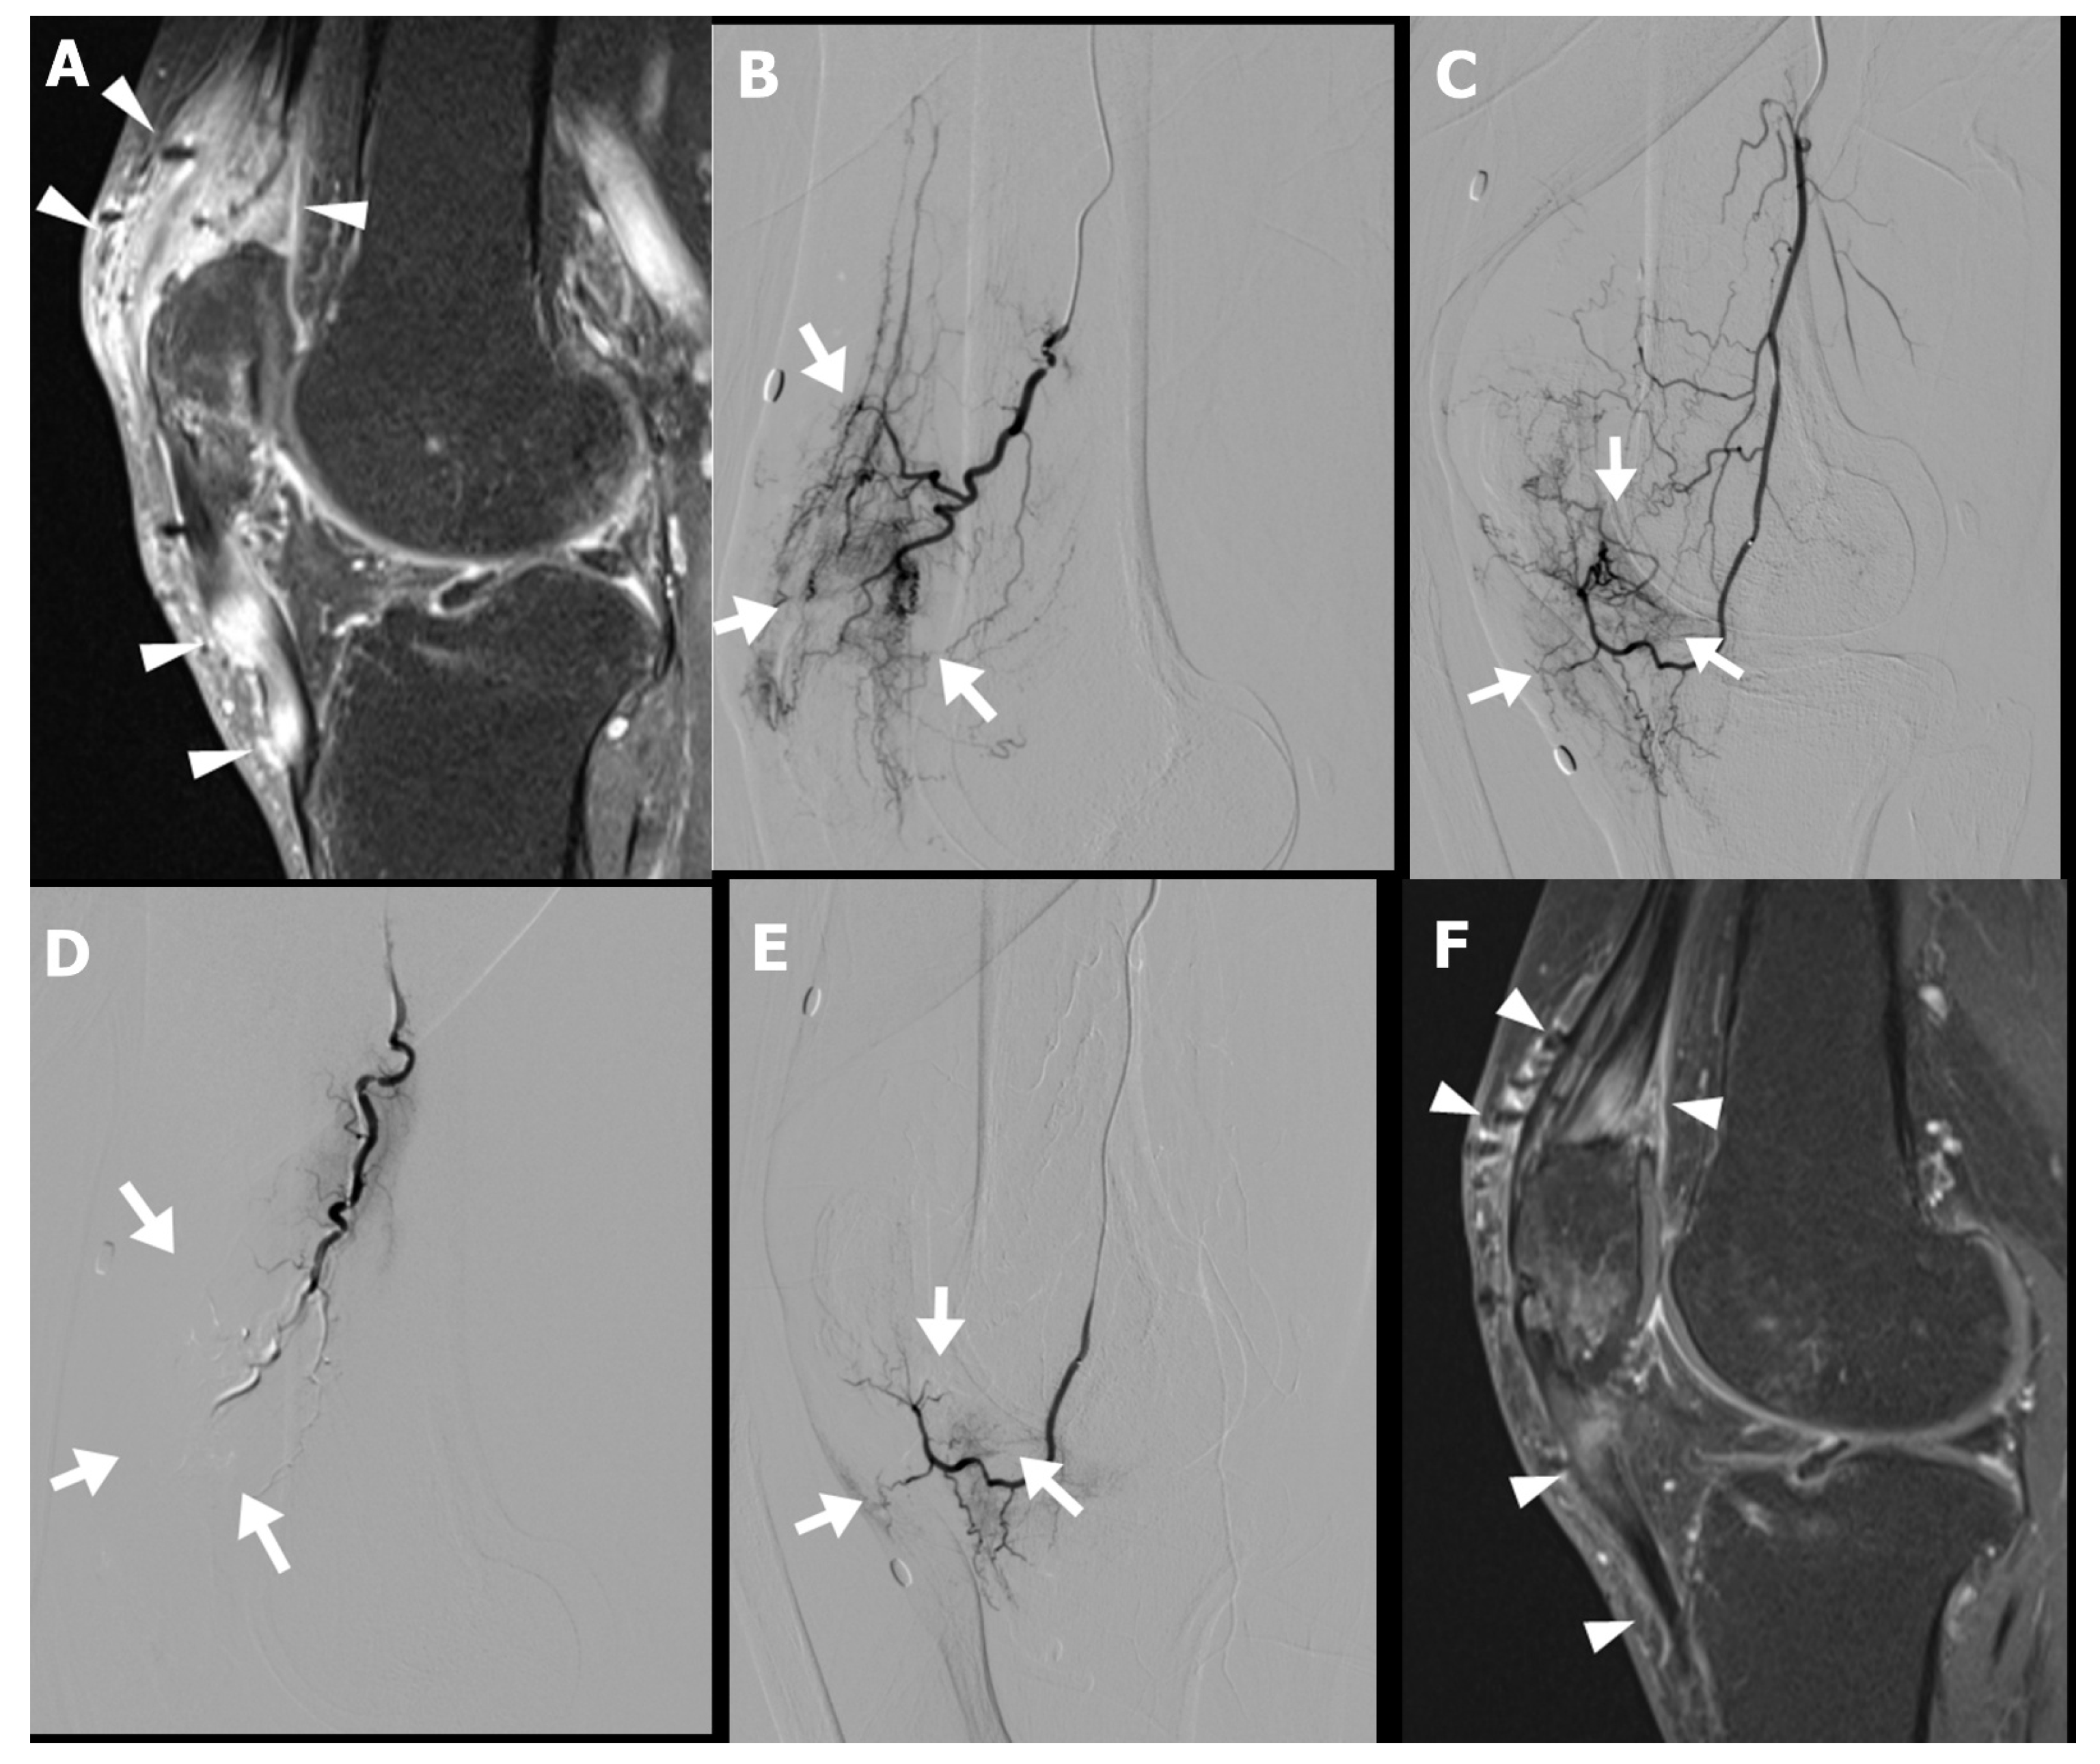

A 63-year-old male patient (Case 6) presented with persistent anterior knee pain following open reduction and internal fixation for a patellar fracture. His symptoms included localized swelling, restricted range of motion, and severe pain exacerbated by squatting or kneeling. Despite undergoing implant removal, followed by three months of physical therapy and oral NSAIDs, his symptoms remained refractory to conventional management.

Musculoskeletal sonography and MRI demonstrated increased peritendinous edema and hyperemia surrounding the quadriceps and patellar tendons (Figure 3A). Diagnostic catheter-based angiography revealed pronounced hypervascularity in the superior patellar artery and descending genicular artery territory (Figure 3B–E). The patient subsequently underwent TAE targeting these vascular territories in two sessions.

Following the procedure, the patient reported gradual improvement in anterior knee pain, with the NRS decreasing from 6 at baseline to 4 at three weeks, and further to 2 at the three-month follow-up. Follow-up MRI demonstrated a marked reduction in both peritendinous and intratendinous angiogenesis (Figure 3F). Clinically, the patient regained full functional capacity, with resolution of swelling and the ability to kneel and squat without discomfort.

Figure 3. Preprocedural gadolinium-enhanced sagittal T1-weighted fat-suppressed magnetic resonance image (MRI) (A) of a 63-year-old male with chronic anterior knee pain persisting for 8 months following patellar fracture fixation demonstrates diffuse peritendinous and intratendinous contrast enhancement involving both the quadriceps and patellar tendons, as well as the adjacent soft tissue (arrowheads). Selective digital subtraction angiography of the superior patellar artery (lateral projection, (B)) and descending genicular artery (lateral projection, (C)) reveals abnormal angiogenesis (arrows in (B,C)) corresponding to the area of inflammation noted on MRI. Postembolization angiography (D,E) shows resolution of the abnormal vascular blush (arrows in (D,E)) indicating successful embolization of the pathological neovasculature. Follow-up MRI at 3 months postembolization demonstrates reduced peritendinous and intratendinous contrast enhancement (arrowheads in (F)), indicating decreased inflammation compared with the pretreatment MRI.